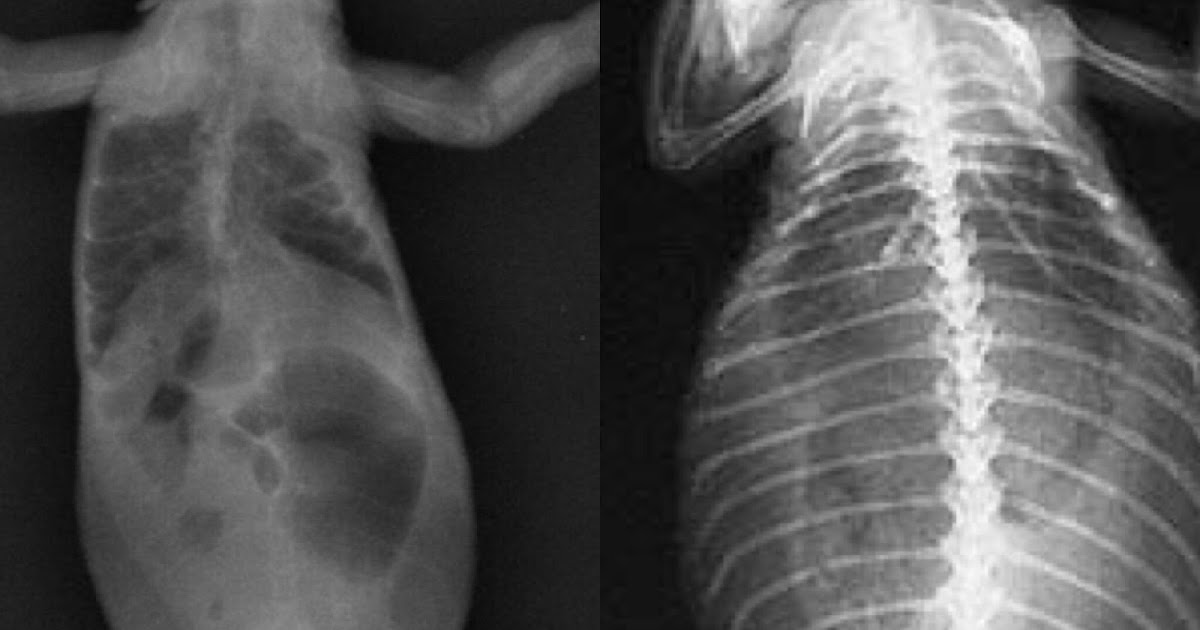

- Soft, rubbery bones

- Bone deformities